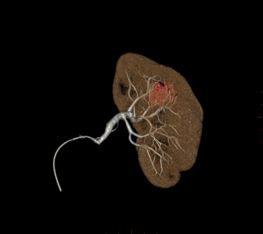

Vessel ASSIST für periphere Verfahren

Bei peripheren, chronischen Komplettverschlüssen (CTO) bietet die Vessel ASSIST-Lösung eine intuitive und genaue Lösung, die Sie bei der Planung und Führung komplexer endovaskulärer CTO-Eingriffe unterstützt. 1

Die automatische Segmentierung von Knochen und Gefäßen und die Mittellinienverfolgung durch den Gefäßverschluss ermöglichen eine schnelle Planung anhand von präoperativen CT- oder MR-Bildern. Durch diese Kombination präoperativer CT- oder MR-Bilder mit Mittellinienverfolgung und Durchleuchtung in Echtzeit können Spezialisten außerordentlich gut sehen, wo die Rekanalisation vorgenommen werden muss und wo sich die Einstichstelle befindet, ohne die Kontrastmittelmenge erhöhen zu müssen.

Vessel ASSIST bietet eine präzise und einfache anatomische Segmentierung und genaue Gefäßquantifizierung anhand von 3D-Volumen. Zudem ermöglichen die erweiterte 3D-Roadmap und erweiterte Bildführungsfunktionen für die frontale und laterale Ebene das sichere Führen von Kathetern.